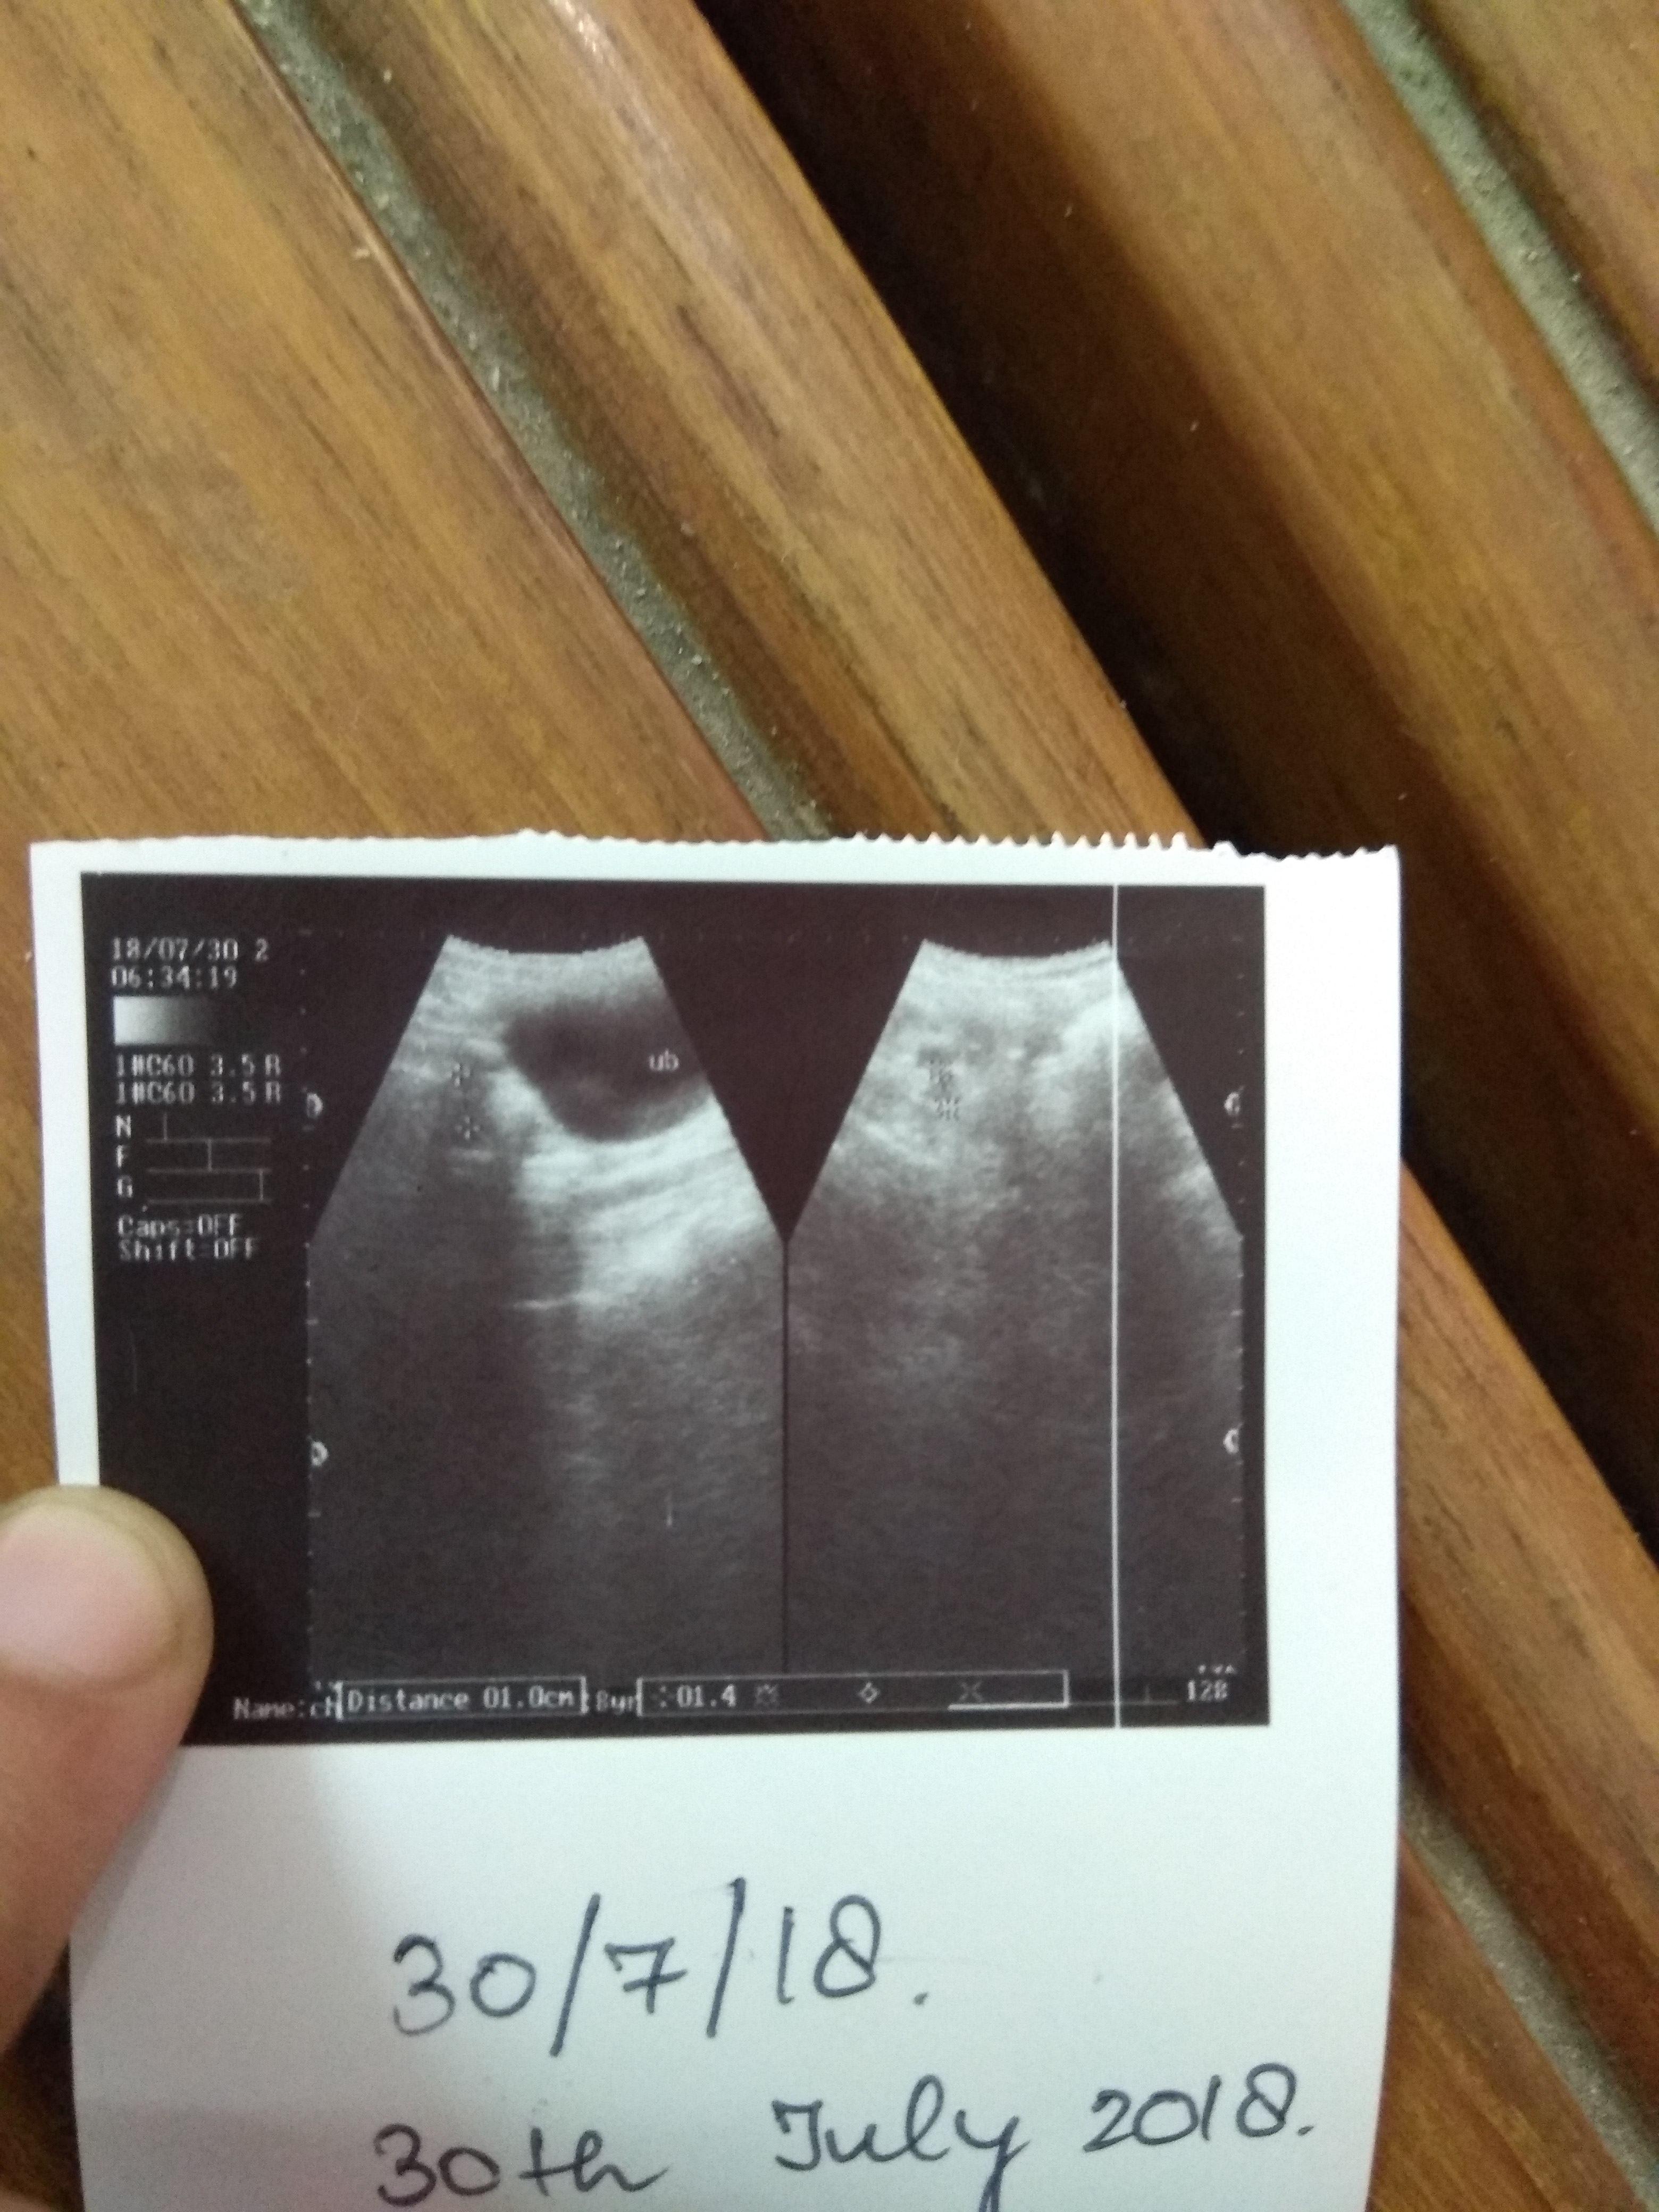

My female dog was having discharge from her vulva then vet gave med for 10 days then told ultrasound then 2nd vet who did ultrasound said vaginitis only n gave vaginal pessary n did ultrasound after a week again n said infection there,surgery is required from ultrasound report.bt I feel Dr is very money minded(from his reviews,attitude).she initially was sometimes off food n sleepy bt now seems normal,active,eating okay.plz see ultrasound pics n tell uterus is visible? discharge is still there.

It's a little difficult to see for certain in the picture, but I do see a fluid filled structure in the photo near the urinary bladder that certainly could be the uterus. In your final picture the discharge on the ground does not look what I would typically expect from vaginitis. You may want to get a third opinion from a veterinarian if you're concerned about going forward with surgery. If it is a uterine infection it is unlikely to clear with antibiotics alone and even if it does the infection returns with the next heat cycle, so I typically recommend surgery whenever I am concerned about a pyometra.

I would recommend to have surgery performed if it is the best recommended option. I would say that there is fluid in the uterus and increased shadowing, it is just a picture so difficult to fully comment. I know it is a surgery but it is very common for dogs to suffer with pyrometers as they get old, so it would prevent her anyway from getting it, hope this helps